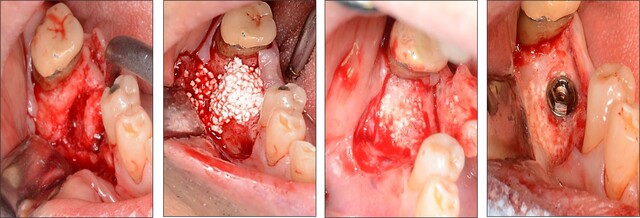

インプラントを行うには人工歯根(インプラント体)を顎の骨に埋め込む必要がありますが、歯を失ってしまうと骨の厚みが減少し、インプラントを安定して埋め込むことができないケースがあります。こうした場合にサイトランスを用いることで約半年で骨が再生し、インプラントを固定できる基盤を作ることが可能になります。

歯が抜けて痩せてしまったところにサイトランスを埋植すると、自身の骨に置き換わって新しい骨を形成し、インプラントの土台を埋め込むことが可能になります。

矯正治療への対応例。